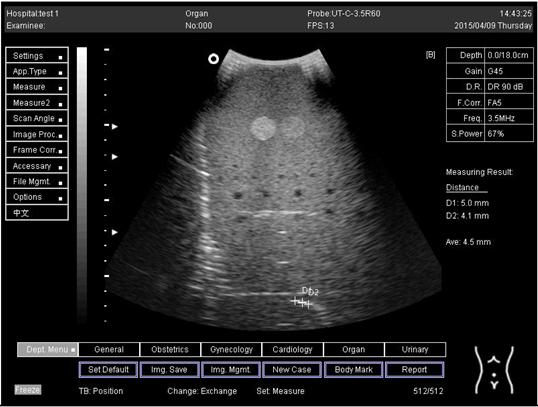

18.0Lateral resolution

Biomimetics 07 00130 i020

D1 = 5.0

D2 = 4.1